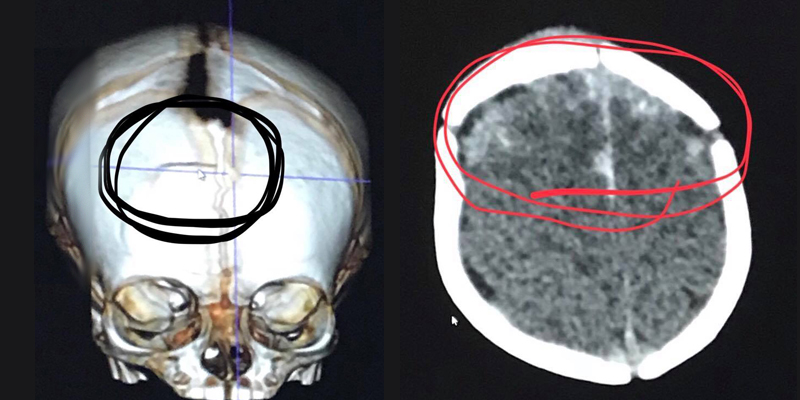

Una pelota de softball golpeó accidentalmente a una pequeña de 7 semanas de nacida y sufrió un fuerte traumatismo en la cabeza, esto pasó mientras su madre le estaba dando de comer.

Siendo tan pequeña, esta niña llamada McKenna Hovenga se encuentra luchando por su vida en un hospital, pues hace apenas un par de semanas recibió un fuerte golpe en la cabeza que le ocasionó un grave daño

La niña sufrió un severo daño en la cabeza mientras Kassy Hovenga, su madre, la amamantaba y de pronto un balón de softball salió disparado ocasionándole fractura craneal. La pequeña fue llevada al hospital de emergencia pero se encuentra muy grave.

Aunque ahora está estable con la atención médica y un respirador artificial, es muy probable que sea trasladada a cuidados intensivos pediátricos. Además de hacer un seguimiento constante de la presión arterial baja que representa, es alimentada por medio de una sonda.